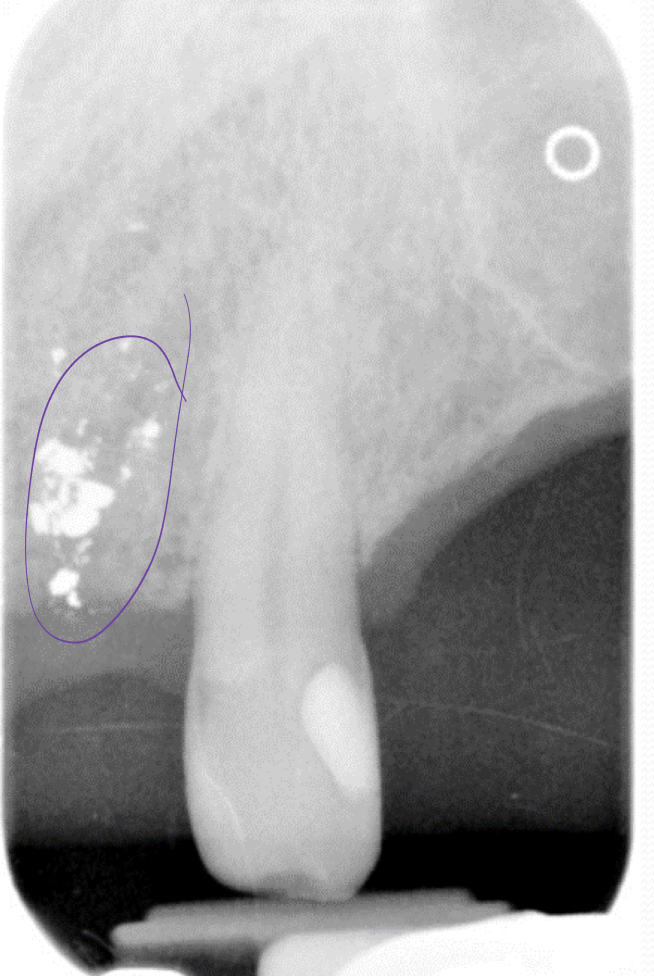

Amalgam fragments